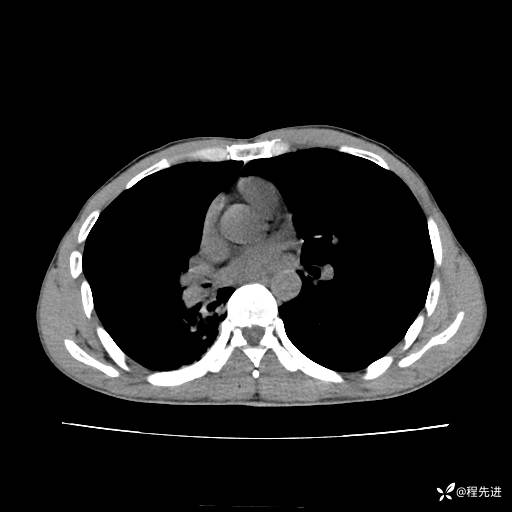

患者性别:男

患者年龄:49岁

主诉:咳嗽、胸痛1周

简要病史:1周前受凉感冒后开始出现咳嗽症状,阵发性连声咳,痰多,黄白痰,不易咳出,伴胸痛、气紧、胸闷,右侧为主,活动用力、呼吸时胸痛明显,曾在当地诊所贴敷膏药仍疼痛

体格检查:T:36.3 ℃ P:80 次/分 R:20 次/分 BP:120/88 mmHg,指脉氧饱和度97%,意识清晰,呼吸平稳,右侧第二、三肋骨压痛,可见膏药贴敷,皮肤无异常,双肺呼吸音粗,未闻及干湿性啰音。心率80次/分,节律整齐,无杂音。腹平软,全腹无压痛无反跳痛

临床诊断:社区获得性肺炎

CT平扫: